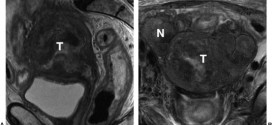

Leer MásTUMOR VESICAL QUE INVADE LA MITAD INTERNA

El tumor vesical que invade la mitad interna (T2a). Tumor maligno en general y especialmente el formado por células epiteliales, a saber. Durante los primeros años de vida de una persona, las células normales se dividen más rápidamente para permitir el crecimiento. El cuerpo está compuesto por billones de células vivas. Las células normales del cuerpo crecen, se dividen formando …